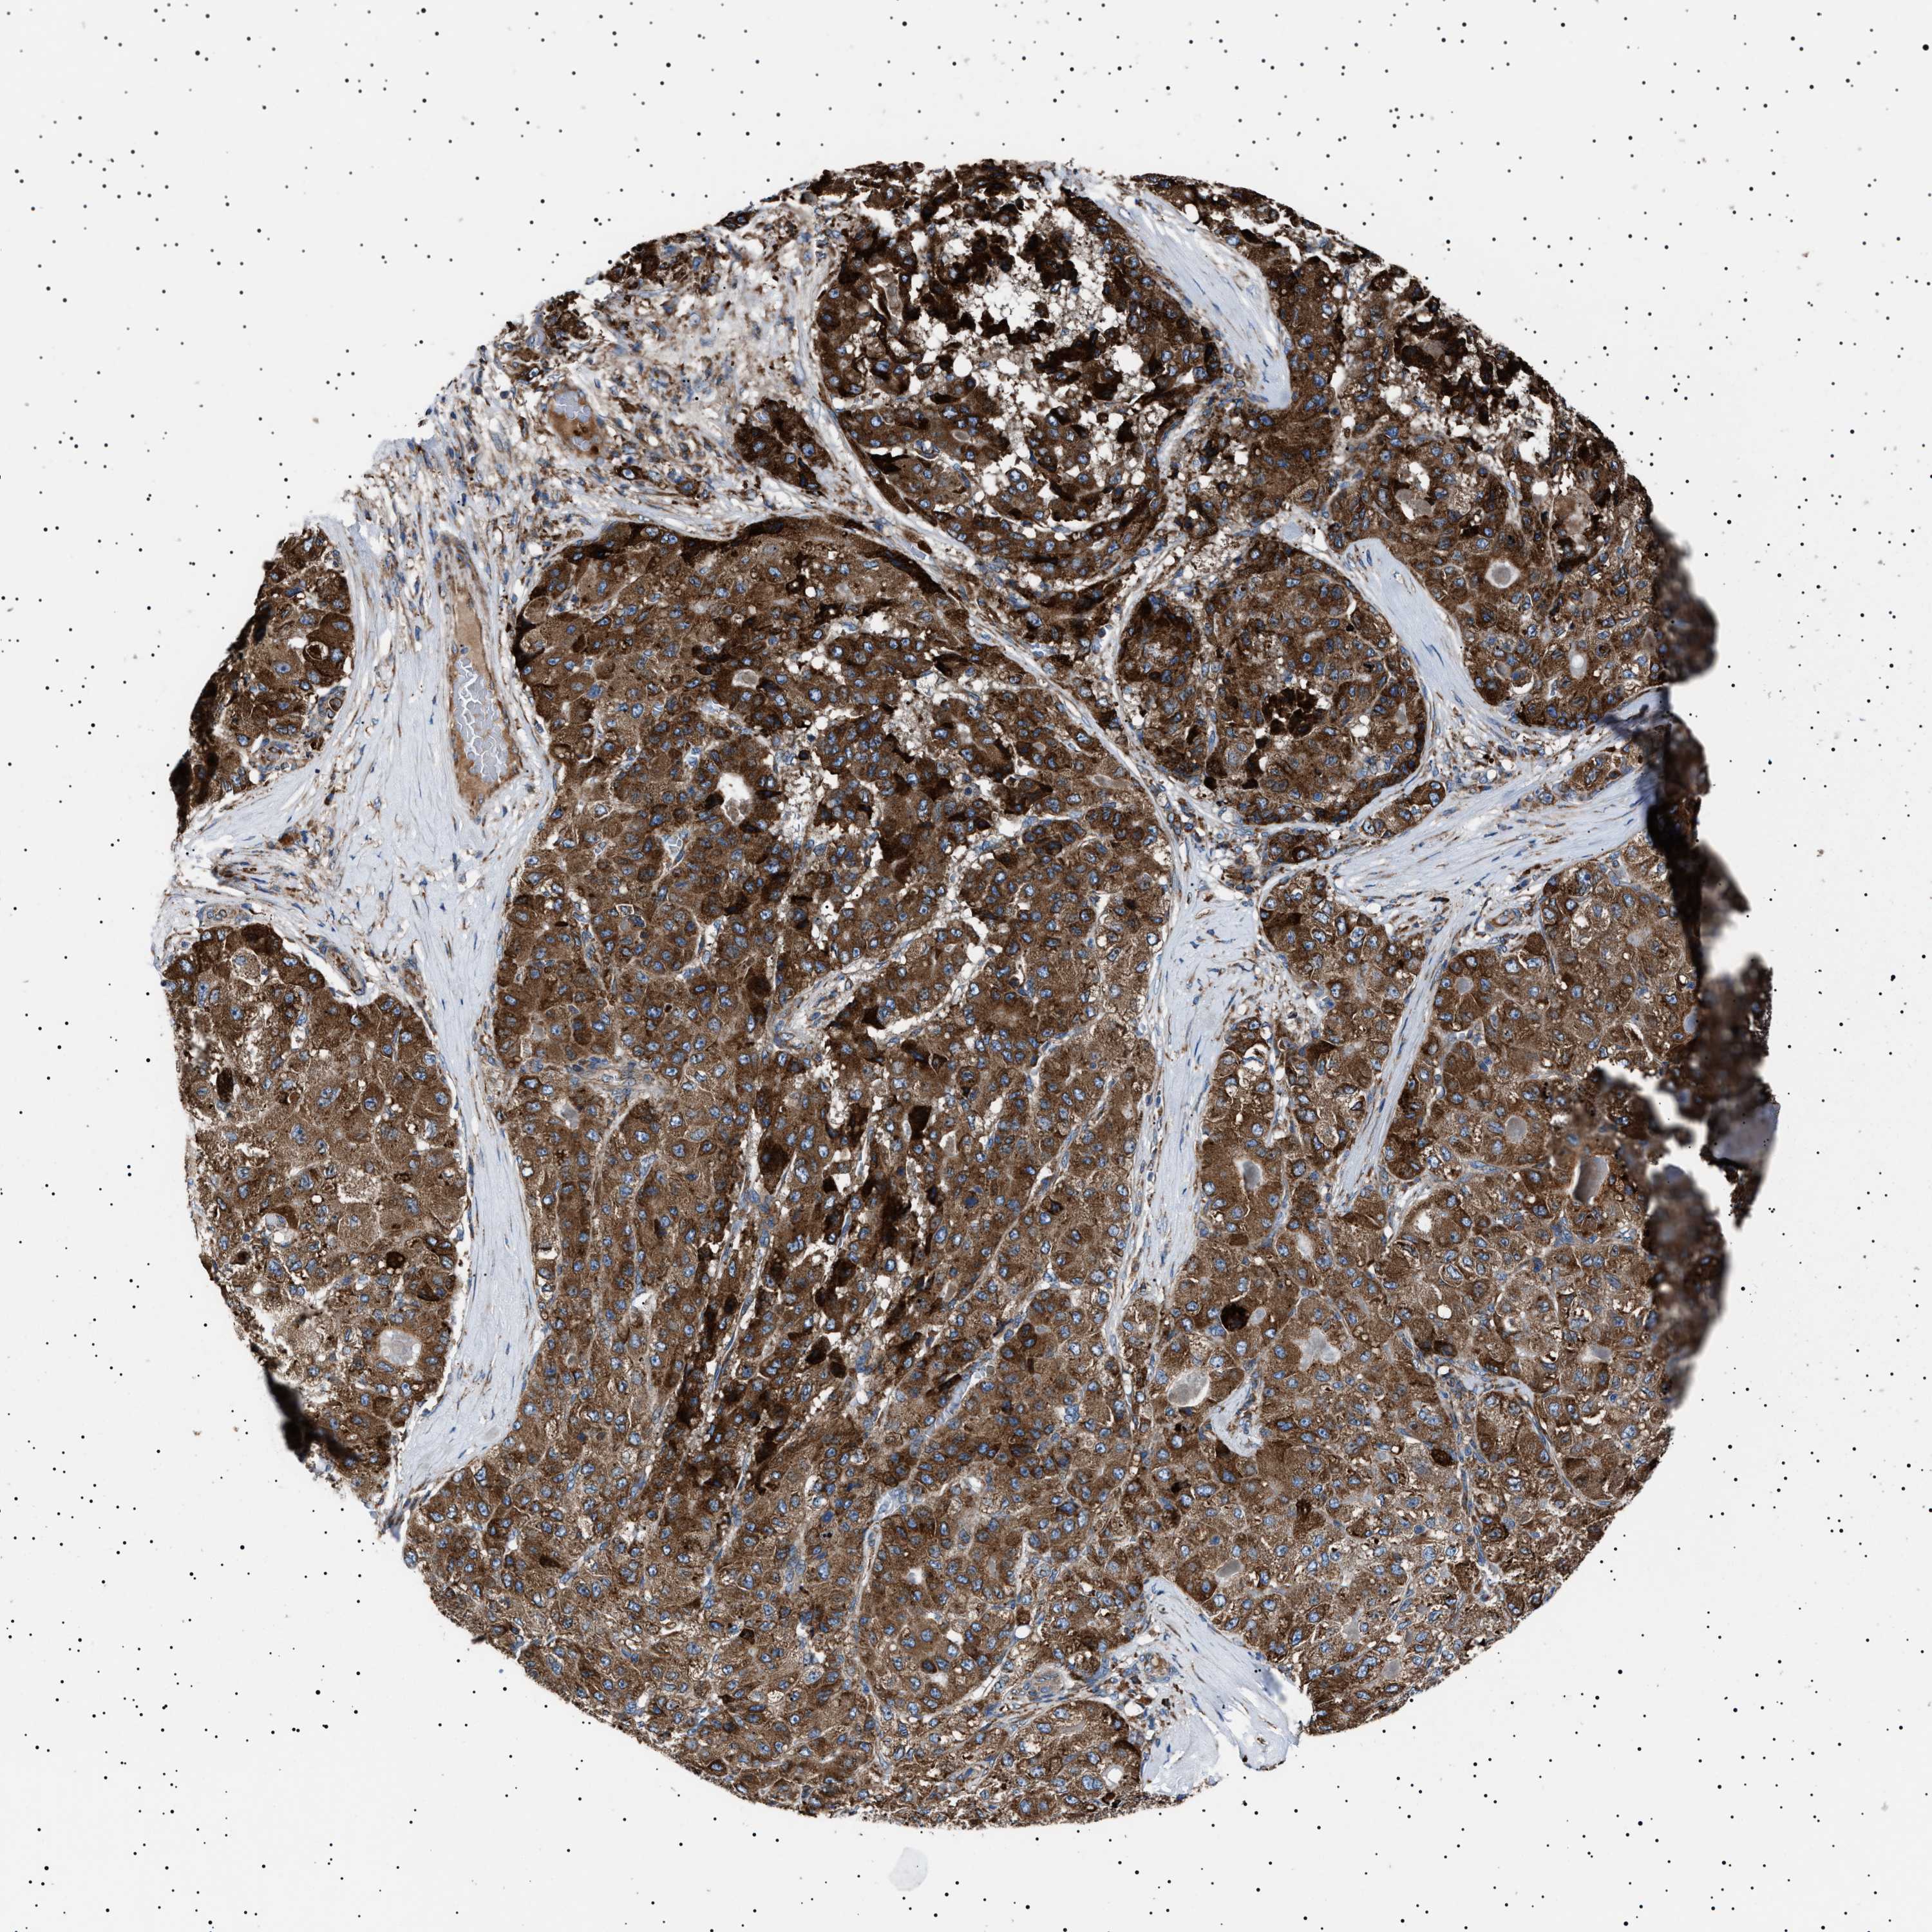

LIVER CANCER - Protein expressioni

A mouse-over function shows sample information and annotation data. Click on an image to view it in a full screen mode. Samples can be filtered based on level of antibody staining by selecting one or several of the following categories: high, medium, low and not detected. The assay and annotation is described here.

Note that samples used for immunohistochemistry by the Human Protein Atlas do not correspond to samples in the TCGA dataset.

Antibody stainingi

Antibody staining in the annotated cell types in the current human tissue is reported as not detected, low, medium, or high, based on conventional immunohistochemistry profiling in selected tissues. This score is based on the combination of the staining intensity and fraction of stained cells.

Each image is clickable and will lead to virtual microscopy that enables deeper exploration of all samples and also displays staining intensity scores, fraction scores and subcellular localization as well as patient and tissue information for each sample.

Antibody HPA001915

Antibody HPA021542

Staining

High

Medium

Low

Not detected

Intensity

Strong

Moderate

Weak

Negative

Quantity

>75%

75%-25%

<25%

None

Location

Nuclear

Cytoplasmic/membranous

Cytoplasmic/membranous,nuclear

Cholangiocarcinoma

Carcinoma, Hepatocellular, NOS